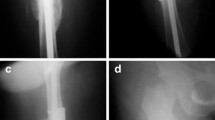

At the last follow-up, the median flexion ROM of the knee was 120°(90°-120.0°). The hip range of movement was normal in all of the patients, and all patient treatment outcomes were considered good (Fig. 2).

Patient #3, a 56-year-old man with Cinery–Mader type IV chronic haematogenous osteomyelitis in the shaft of the right femur. A: Pre-operative anteroposterior (AP) radiograph of the right femur; B: Pre-operative lateral X-ray of the right femur; C: Pre-operative CT shows bone destruction; D: Pre-operative bone radionuclide scintigraphy; E: Radiograph shows that the lesion was segmentally resected, the bone defect was filled with antibiotic-loaded bone cement, and a cement-coated locking plate was used as temporary stabilisation at T1; F: Wound healing before T2 surgery; G: After the bone cement was removed, an intact induced membrane could be observed. H & I: Radiograph shows an IMN and a locking plate that were used as definitive fixation after T2 surgery; J & K: Callus growth was observed after 5 months; L & M: AP and lateral radiographs show bone union after 30 months; N & O: Radiographs after 52 months